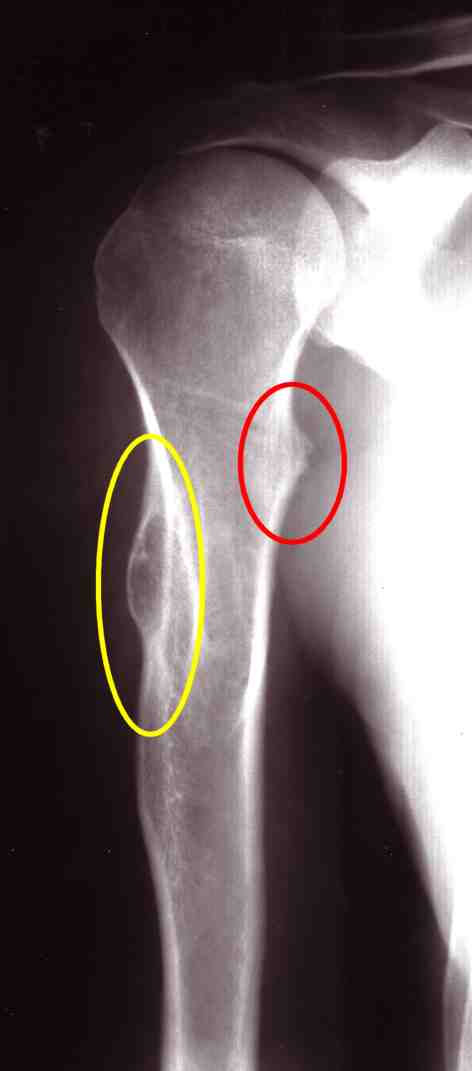

Aber erstmal ab unter den großen Fotoapparat um mal zu sehen, wie es in mir wirklich aussieht. Auf dem ersten Bild war der, der mich damals störte (gelb) relativ groß, aber recht rund. Aber an der Unterseite (rot) sah ich eine recht kleine spitze Zacke. Klar..das schmerzt, wenn sich die in den Muskel bohrt.

Auf dem zweiten Bild - der Arm ist hier gedreht - zeigt sich die wahre Größe von der "kleinen" Spitze. Das Dingen ist gute 12 Zentimeter lang und etwa 2,5 Zentimeter raus stehend

. Und so bestand auch kein Grund zum diskutieren...die Überweisung in die Klinik folgte sogleich. Ich werde mich im November dor vorstellen und mich dann - wenn es klappt - im Januar oder Februar mal wieder aufschneiden lassen.